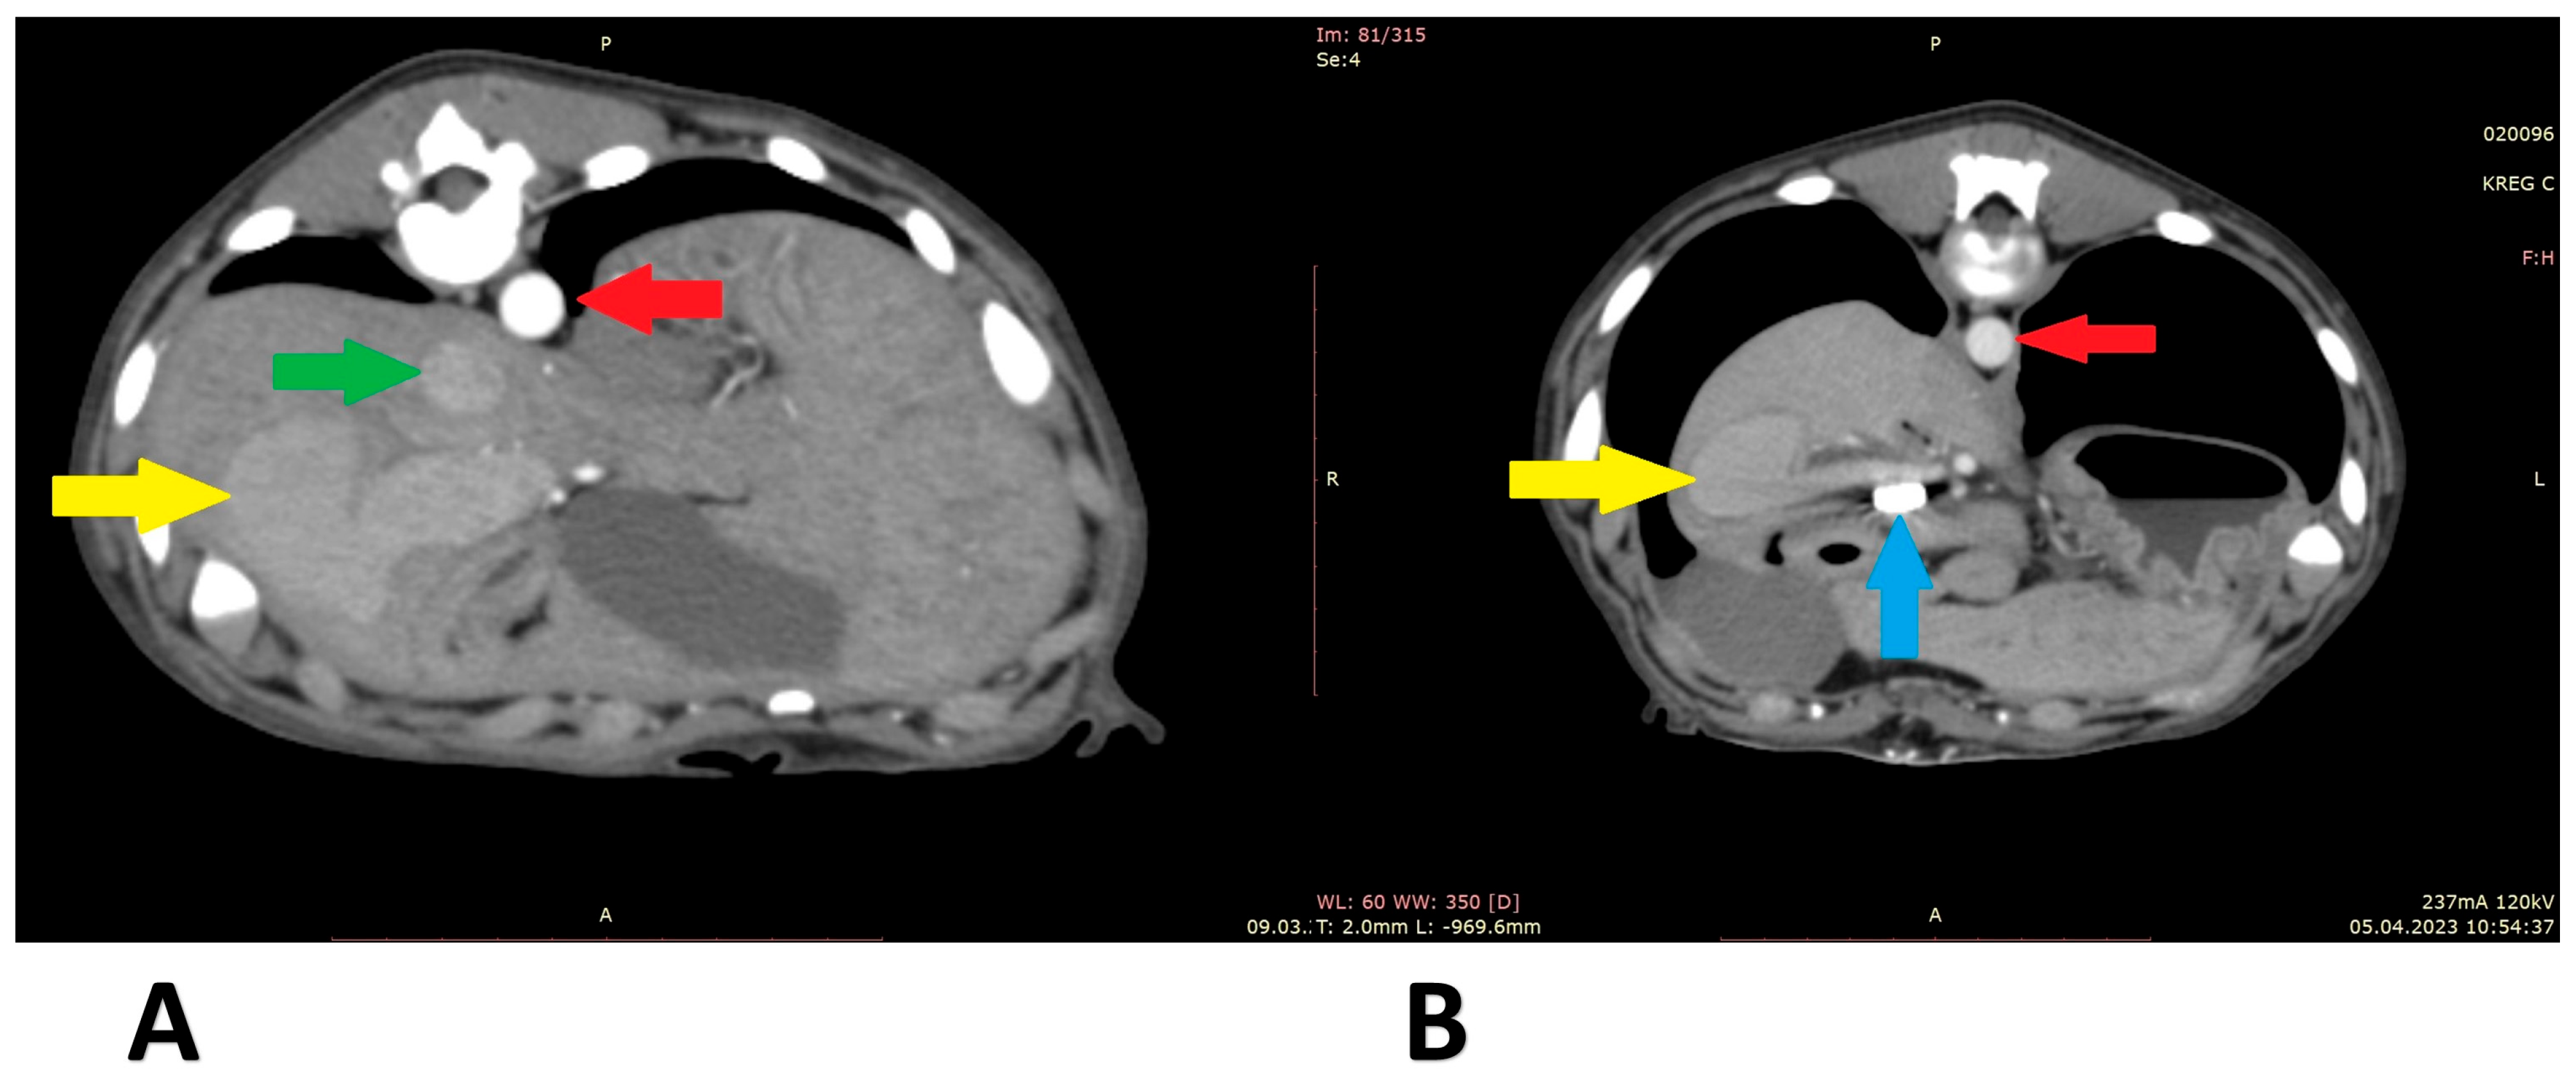

A 6-month-old, male, mix-breed with a right divisional shunt, diameter 12 mm, connecting the right lateral hepatic vein to the caudal vena cava. Attenuation was performed with a cellophane band and confirmed on postoperative CTA. Figure 5 shows the stages of the shunt visualization. Figure 6 presents CTA scans of the shunt before and immediately post attenuation. The patient showed a good clinical response. At the time of writing, the dog is 2 months post operation.

Figure 6.

Computed tomographic angiography scans (patient 4): (A) before shunt attenuation; (B) post attenuation. Red arrow: aorta; green arrow: caudal vena cava; yellow arrow: shunt; blue arrow: vascular clips keeping the cellophane band in position.